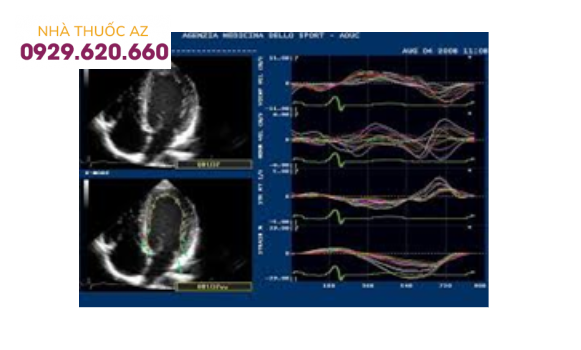

Doppler đánh dấu mô (speckle tracking) đánh giá sức căng theo trục dọc của thất trái và tình trạng tưới máu cơ tim thất trái